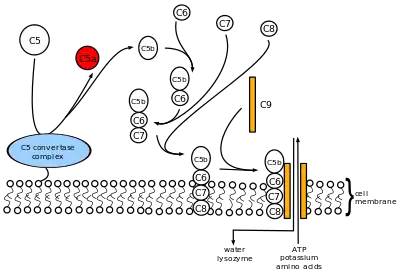

Complement component 5 is involved in the complement system. It is cleaved into C5a and C5b:

- C5b forms the first part of the complement membrane attack complex.

Complement component 5 is the fifth component of complement, which plays an important role in inflammatory and cell killing processes. This protein is composed of alpha and beta polypeptide chains that are linked by a disulfide bridge. An activation peptide, C5a, which is an anaphylatoxin that possesses potent spasmogenic and chemotactic activity, is derived from the alpha polypeptide via cleavage with a C5-convertase. The C5b macromolecular cleavage product can form a complex with the C6 complement component, and this complex is the basis for formation of the membrane attack complex, which includes additional complement components.[5]